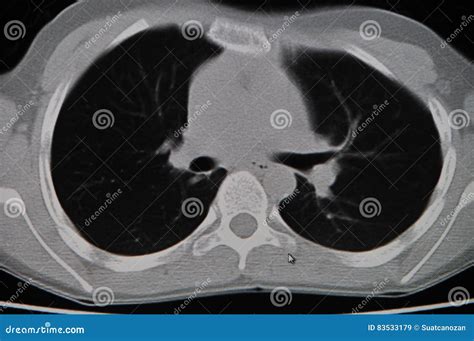

Ct Chest Normal

A CT scan of the chest uses X-ray technology coupled with computer processing to create cross-sectional images of the lungs, heart, airways, mediastinum, and chest wall. When a report is labeled as a Ct Chest Normal, it signifies that the diagnostic structures within the thorax appear within standard anatomical limits. This does not necessarily mean you are without illness, but rather that the specific structural components visible on the scan do not show evidence of tumors, infections, significant blockages, or other major structural pathologies at the time of the scan.